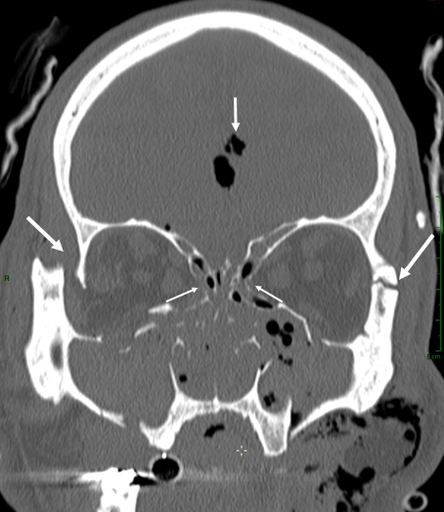

Anatomie et pathologie de l’orbite

Orbite